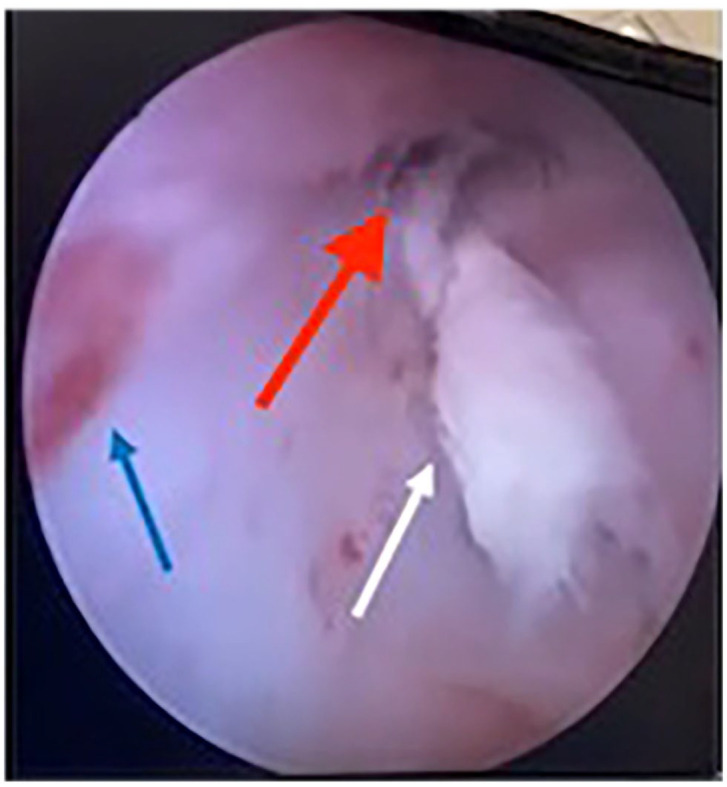

Case summary: A 2-year-old domestic shorthair queen sustained a tear in the vaginal wall through which the queen herniated a fetus during parturition. An exploratory laparotomy was performed, the patient had an ovariohysterectomy and the fetus was removed vaginally. The tear was managed medically with antibiotics, analgesics and careful monitoring. Assessment of the injury site 2 weeks later confirmed successful healing without the need for surgical intervention in the vaginal wall.

Relevance and novel information: This is the first report in veterinary medicine describing the successful medical management of a dystocia-related vaginal wall tear in a feline patient without surgical repair.